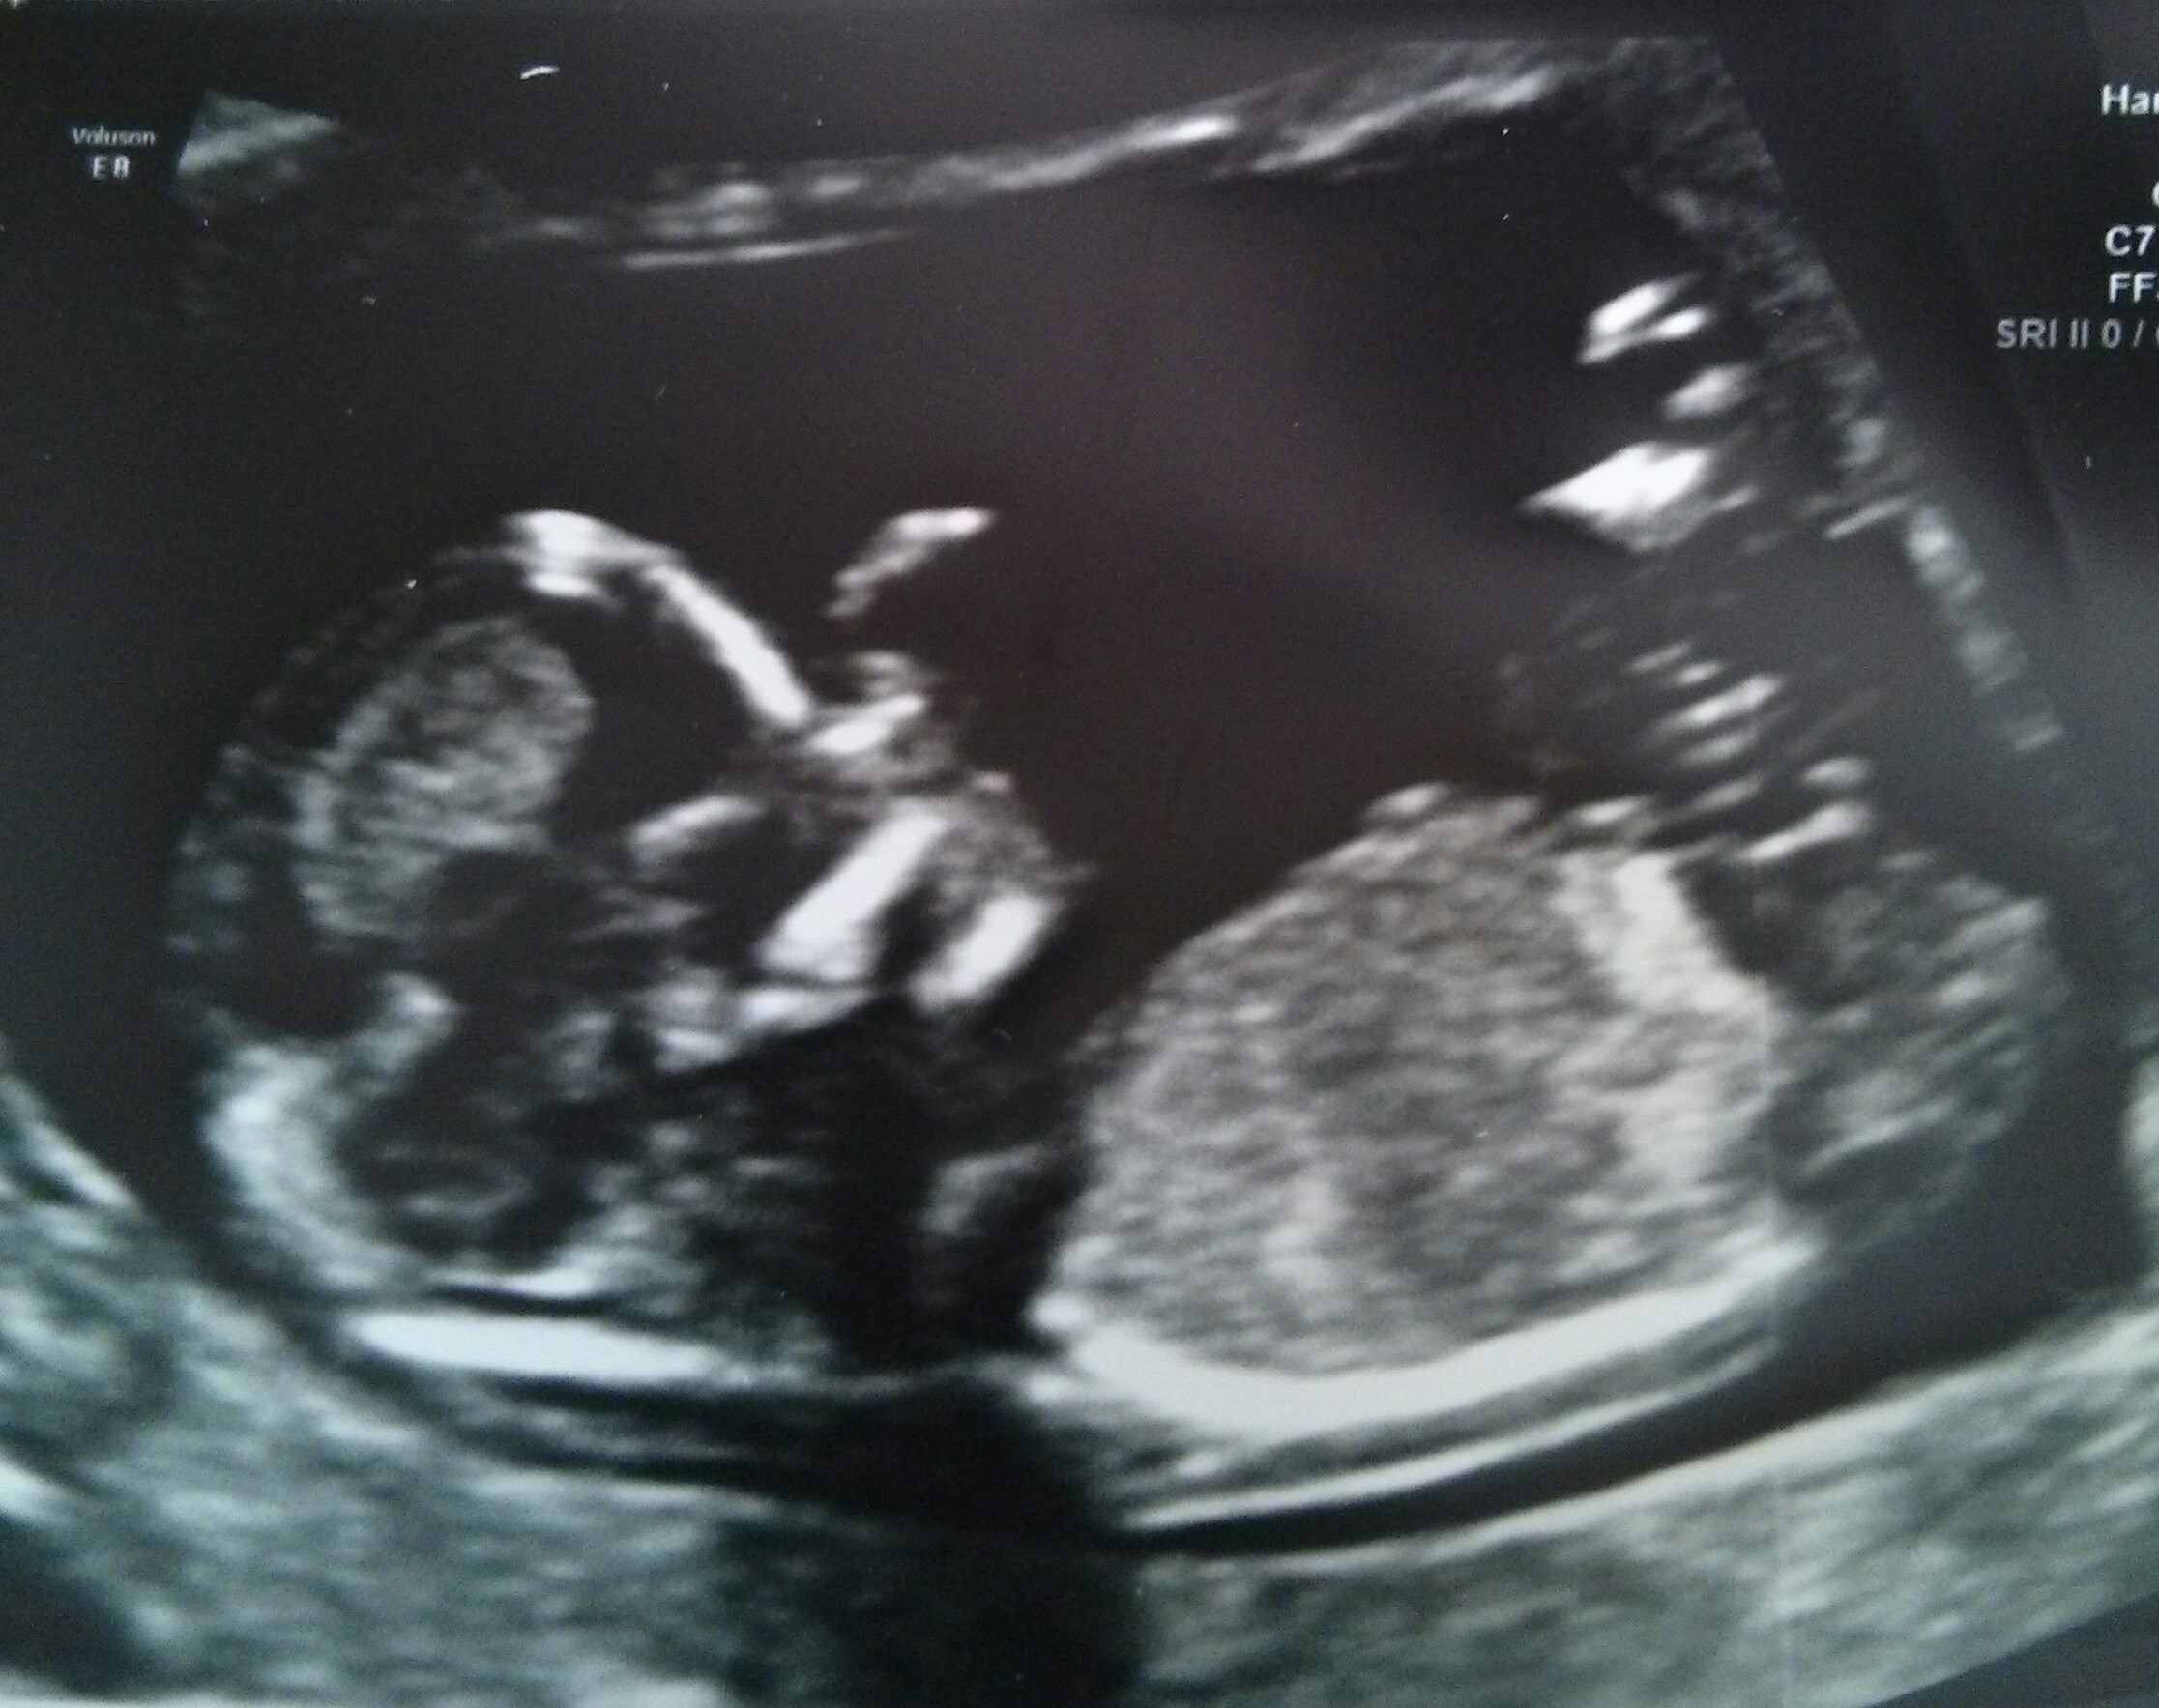

Here's my ultrasound pic for 12W5D. I have no idea if nub is visible or not, but looks girly to me. What do you think? Attachment 18091Attachment 18092

I think I see a boy nub in the 2nd pic.

Agree with the other posters plus it's hard to tell if all of the nub has been captured. Tentative blue lean! Congratulations xx

Guessing blue.

guessing blue too

Boy guess from me too.

Guessing boy as well :)

I think maybe boy too....tho it is pretty busy down there and it's not overly clear...

I think you have a blue bundle!